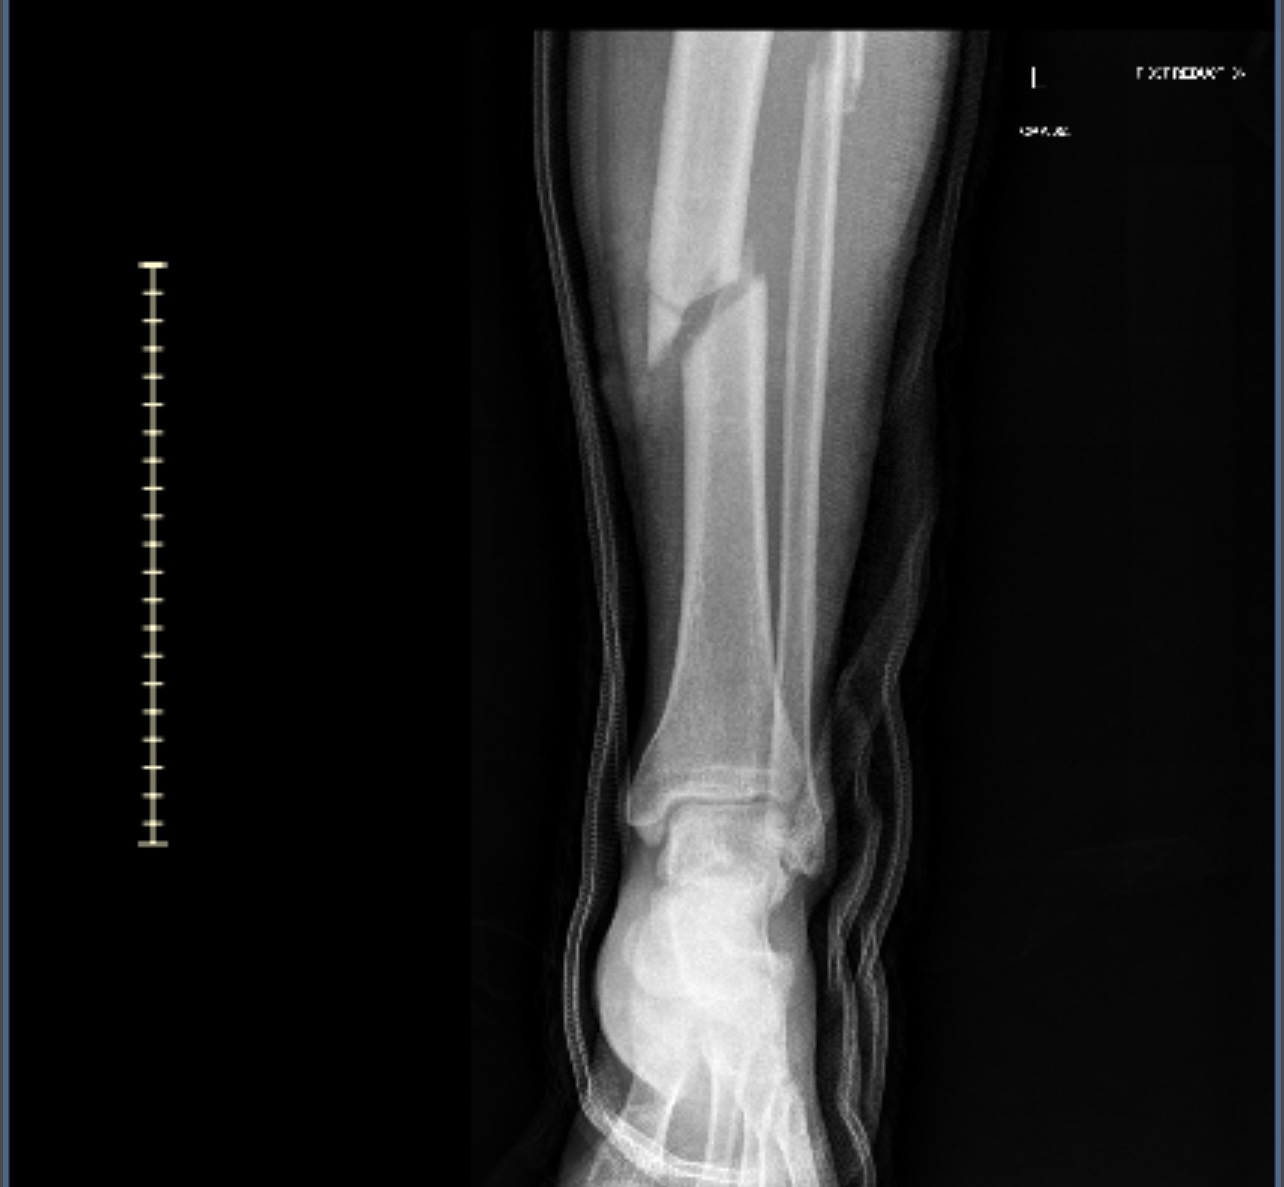

A few days ago, our beloved brother, Edgar, suffered a serious accident while working on a home project. He fell 25 feet off a ladder, resulting in a broken tibia, fractured spine, and a fractured foot. injuries that now require extensive recovery and time away from work.

Hace unos días, nuestro querido hermano, Edgar, sufrió un accidente grave mientras trabajaba en un proyecto de casa. Se cayó a 25 pies de una escalera, lo que resultó en una tibia rota, la columna fracturada y un pie fracturado. Lesiones que ahora requieren una recuperación extensa y tiempo fuera del trabajo.